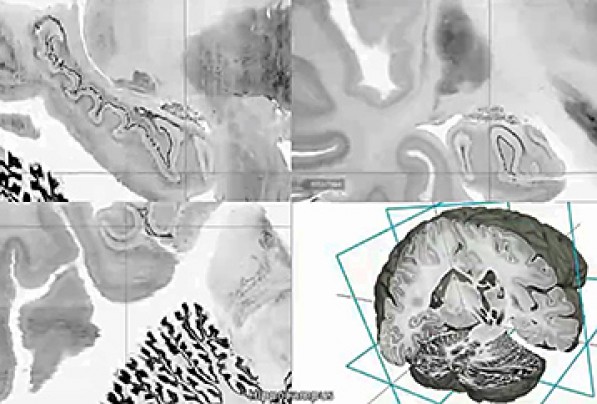

The digital three-dimensional model called "BigBrain" was produced from the thousands of sections made from the brain of a 65-year-old woman. Its resolution is finer than a human hair, so it can reveal clusters of brain. A 65-year-old woman’s brain was cut into 7,400 slices to create the most detailed three-dimensional atlas of the human brain ever made, bringing researchers one step closer to reverse-engineering the brain’s convoluted circuitry. Brain atlases are essential reference tools for researchers and physicians, to determine which areas are “l(fā)ighting up” during a task or thought process, or during image-guided surgery. The better the atlas resolution, the better doctors can target ever-smaller parts of the brain and their individual function. The atlas creators, who are from Canada and Germany, have made the ultrahigh-resolution model — 50 times more detailed than a typical scan — publicly available in a free online format. The authors also published their work in the journal Science on Thursday. The atlas, called BigBrain, offers a common basis for open, worldwide scientific discussion on the brain, said author Karl Zilles of the Heinrich Heine University Düsseldorf. Zilles pointed to a novel treatment for Parkinson’s disease called deep brain stimulation, where electrical impulses are sent through electrodes implanted into specific points in the brain. He said BigBrain may open the doors for more accurate localization of electrode placement and thus render treatment more effective. After staining and digitizing the thousands of plastic-wrap-like slices, the nearly cellular resolution map revealed the network of layers, fibers and microcircuits of the woman’s brain. While variation exists among brains, across ages and individuals, they have largely the same distribution of brain structures and anatomy, said author Alan Evans of McGill University’s Montreal Neurological Institute. There are “subtle shape changes among individuals,” but all atlases start from one representative brain and go from there. The team was chiefly limited by computing power and capacity. To map the human brain with 1 micron spatial resolution, which has been done for mouse brains, the atlas would take up 21,000 terabytes of data — essentially rendering it impossible to navigate. By comparison, BigBrain, with its 20 micron resolution, comprises about a terabyte of data. Prior MRI-based atlases had resolution of 1 millimeter. Richard Leigh, a Johns Hopkins neurologist, said he’s looking forward to test-driving BigBrain for his research on stroke recovery. With the microscopic detail available, Leigh can see which particular groups of neurons are growing through stroke treatment rather than just a general fuzzy area. Evans was in Seattle on Wednesday working with the Allen Institute for Brain Science. Created by Microsoft co-founder Paul Allen, who has committed $500 million since its start in 2003, the Allen Institute has assembled a less-detailed human brain atlas of its own. BigBrain is part of the European Union’s Human Brain Project that brings together specialists in neuroscience, medicine and computing to decipher the mysteries of the brain. President Obama announced in April an initiative to map the human brain, describing it as a way to discover cures for neurological disease and strengthen the economy. |

據(jù)《華盛頓郵報(bào)》6月21日?qǐng)?bào)道,科學(xué)家成功繪制出有史以來(lái)分辨率最高的3D人腦圖譜。這意味著,研究人員在大腦回路逆向工程方面的研究更進(jìn)了一步。 大腦圖譜是科研人員和醫(yī)生必備的參考工具,通過(guò)圖譜,他們可判定在工作、思維過(guò)程中,或是在圖像導(dǎo)航的外科手術(shù)過(guò)程中,大腦哪個(gè)區(qū)域在變化。圖像分辨率越高,醫(yī)生就能更好地聚焦大腦微小的部位,研究它們各自的功能。 加拿大和德國(guó)的研究人員制作了這份大腦圖譜,并于6月19日在《科學(xué)》雜志上發(fā)表。他們將一名已故的65歲女性的大腦切成7400片,將切片染色并進(jìn)行數(shù)字化處理,最終生成高清模型,清晰地呈現(xiàn)出這名女性大腦的皮層、纖維和微電路結(jié)構(gòu)。大腦圖譜分辨率比普通掃描的精度高出50倍,并在網(wǎng)上對(duì)公眾免費(fèi)開(kāi)放。德國(guó)杜塞爾多夫海因里希·海涅大學(xué)的卡爾·齊勒斯稱,該圖譜名叫“大腦”(BigBrain),它為在世界范圍內(nèi)公開(kāi)對(duì)大腦進(jìn)行科學(xué)討論提供了基礎(chǔ)。 齊勒斯指出,帕金森綜合癥有一種新治療方法叫“深部腦刺激”,該方法通過(guò)植入大腦特定部位的電極輸出電脈沖。他說(shuō),“BigBrain”能使電極植入的部位更精確,使治療更有效。 麥吉爾大學(xué)蒙特利爾神經(jīng)學(xué)研究所的艾倫·埃文斯稱,由于年齡和個(gè)體不同,大腦也會(huì)有所不同,但人腦的結(jié)構(gòu)有很大的共性。大腦“因個(gè)體不同會(huì)有微妙的形態(tài)變化”,但萬(wàn)變不離其宗。 這個(gè)研究團(tuán)隊(duì)受到計(jì)算機(jī)能力和容量的局限。研究人員曾繪制分辨率為1微米的老鼠大腦圖譜,但如果要繪制同樣精確的人腦圖譜,將占用2.1億億字節(jié)的數(shù)據(jù)空間,基本不可能用來(lái)作圖像導(dǎo)航。相比之下,“BigBrain”的分辨率是20微米,約占1萬(wàn)億字節(jié)的空間。而此前磁共振成像(MRI)繪制的大腦圖像精度是1毫米。 約翰·霍普金斯大學(xué)神經(jīng)學(xué)家理查德·利表示,他期待將“BigBrain”用于他的中風(fēng)康復(fù)研究。有了更清晰的大腦微觀圖像,利就可以觀察到,在中風(fēng)治療期間,哪些特定的神經(jīng)元簇有所生長(zhǎng),這比看起來(lái)模糊一片要好得多。 埃文斯6月19日在美國(guó)西雅圖和艾倫腦科學(xué)研究所一起工作。2003年,微軟公司的創(chuàng)始人之一保羅·艾倫出資5億美元,聯(lián)合建立了艾倫腦科學(xué)研究所。目前,該研究所已繪制了自己的人腦圖譜,但是分辨率稍低。 BigBrain是歐盟“人腦工程”的一部分,該工程集中了一批神經(jīng)學(xué)、醫(yī)學(xué)和計(jì)算機(jī)領(lǐng)域的專家,欲破解大腦之謎。今年4月份,美國(guó)總統(tǒng)奧巴馬曾宣布了一項(xiàng)大腦圖譜工程,他認(rèn)為,該計(jì)劃可以找到治愈神經(jīng)疾病的方法,還可以振興美國(guó)經(jīng)濟(jì)。 相關(guān)閱讀 巴黎印發(fā)游客服務(wù)手冊(cè) 旨在改善排外形象 斯諾登曝美國(guó)國(guó)家安全局曾密集攻擊清華大學(xué) (翻譯:聞竹 編輯:Julie) |